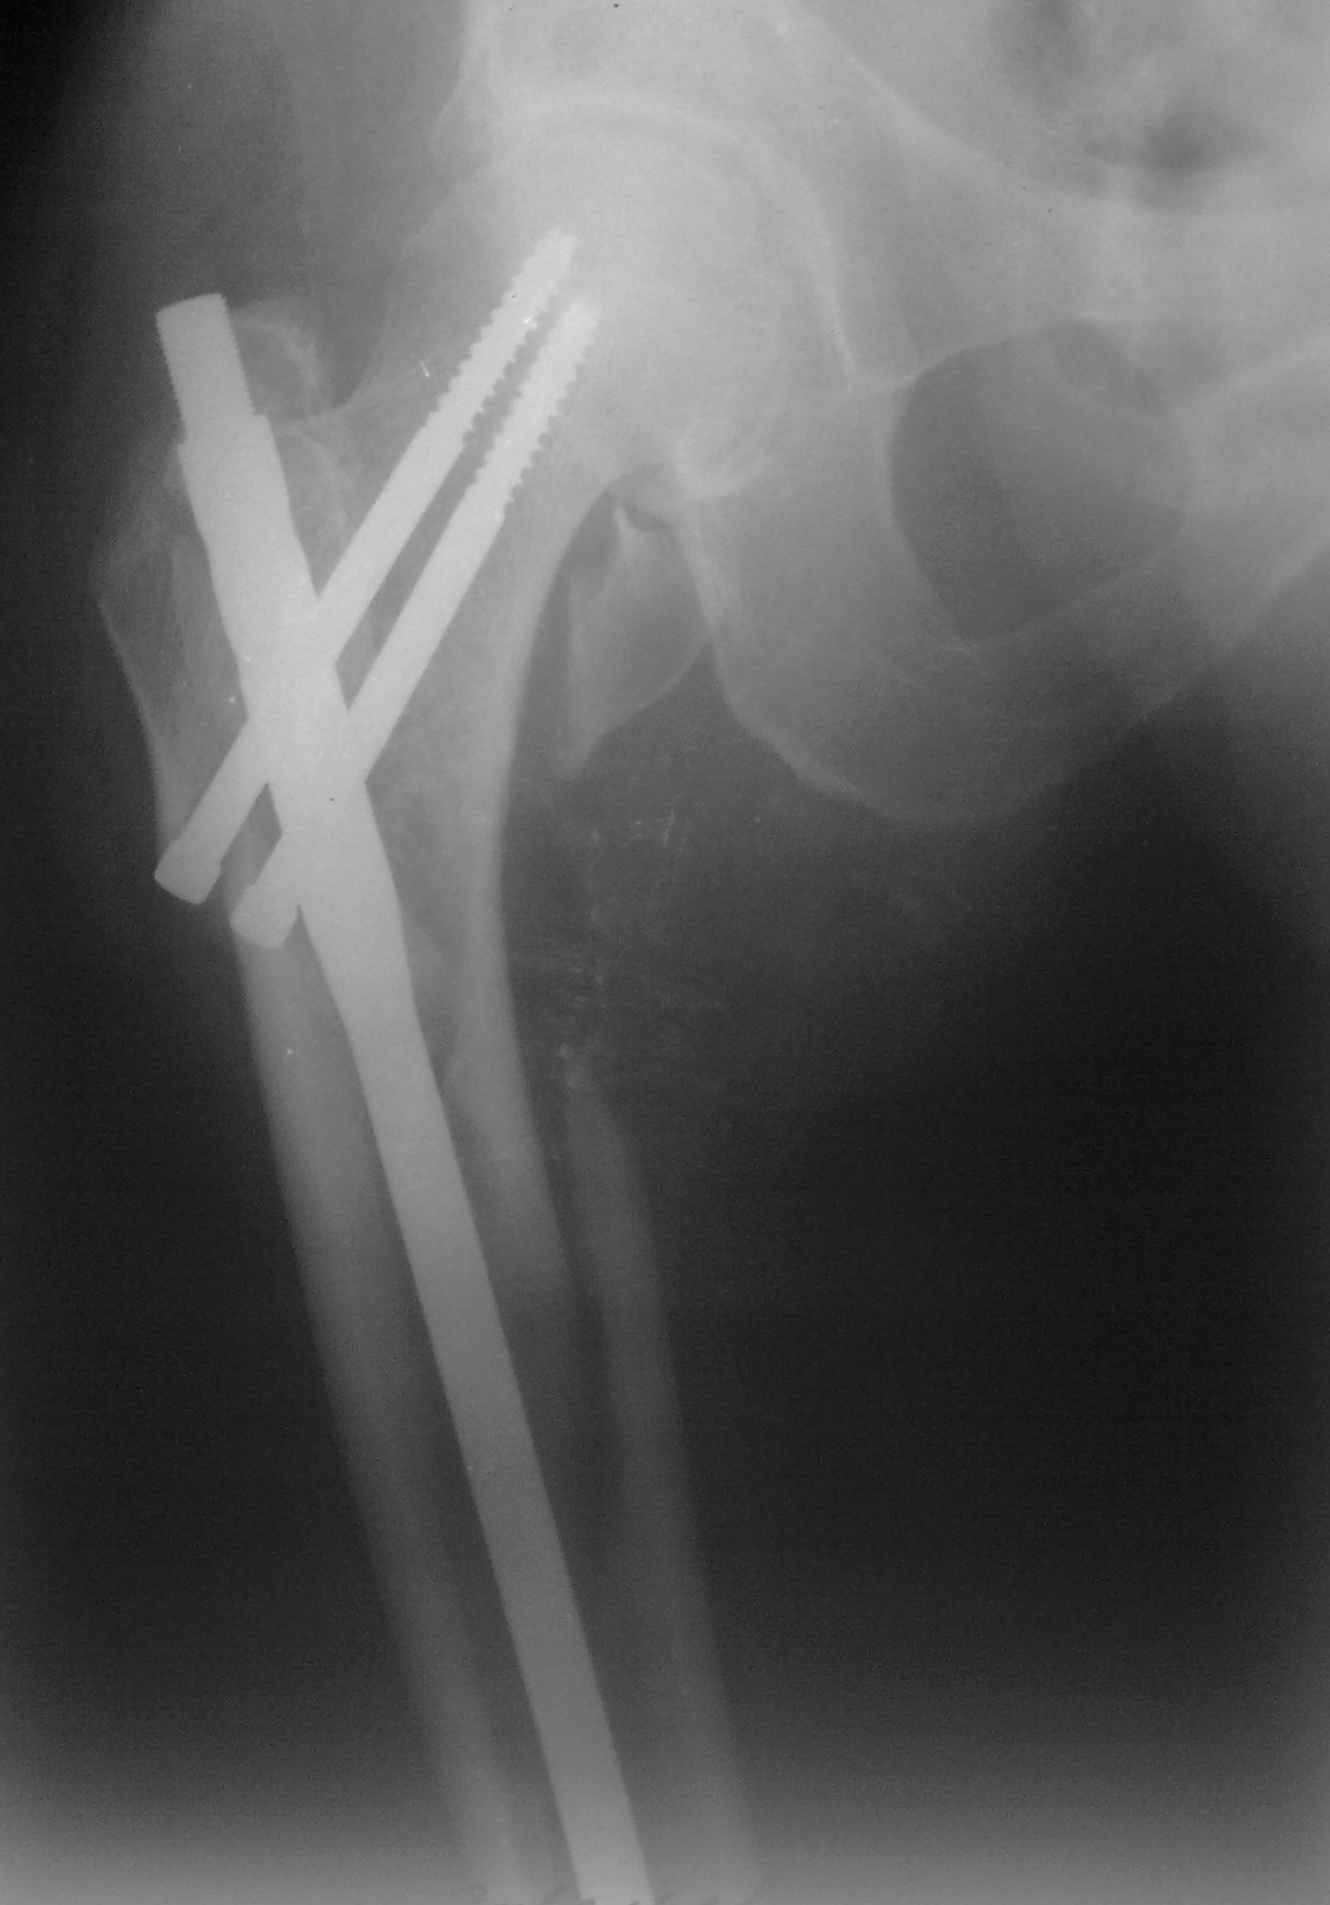

Мда...не самый удачный случай для начинаний... Думаю, 260 мм здесь явно не подойдет(коротковат), перед разрезом добивайтесь максимально возможной репозиции на столе, определитесь с точкой введения штифта(это принципиальный момент), если физически этой точки не существует, то все равно вводите штифт через то место, где она должна была бы быть, постарайтесь вводить штифт ориентируясь по наружному кортикалу и ни в коем случае не идите диагонально. Сам клинок вводите под контролем в аксиальной проекции (естессно, сначала смотрим спицу в прямой). Удачи!)))

И еще: перед разрезом сориентируйтесь и отметьте маркером- ось дистального фрагмента (ориентир для ввода в него штифта), границы большого вертела. Важно ввести штифт в проксимальный фрагмент строго по его анатомическим ориентирам. Для этого устраните его смещения при помощи джойстиков или полуоткрытым способом (костодержателем) и в достигнутом положении вводите штифт.